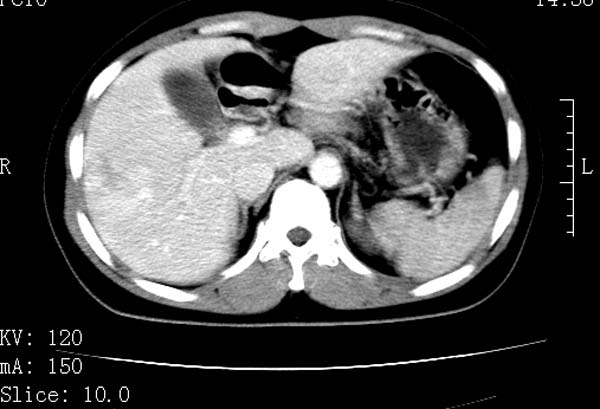

标题: CT22086:女44岁 肝右叶占位增强示巨大血管瘤,门脉期发现小 [打印本页]

标题: CT22086:女44岁 肝右叶占位增强示巨大血管瘤,门脉期发现小

支持肝右叶血管瘤诊断。 小病灶亦考虑血管瘤改变。温习一下:

肝海绵状血管瘤ct平扫常呈均匀低密度,与邻近血管密度相仿。在脂肪肝背景下可呈相对高密度。在增强扫描时,一般早期(动脉期)呈周边结节状或弧形强化,其密度与同层面的血管密度相仿,随着时间延迟向中央渐进性充填,注药后5~7分钟,逐渐扩大至全瘤强化,强化密度逐渐降至稍高于或等于正常肝脏。大的血管瘤往往中央有星形、大的低密度区,可以为纤维化或囊性变所致,纤维化成分可在延迟2 o分钟时完全充填,呈等密度,但囊变区则不会强化。不典型ct表现常见于≤3 cm的小血管瘤。小的血管瘤可以在动脉期即呈全部致密的均匀强化,不呈典型的周边结节状强化表现,但其密度往往较高,与主动脉相仿,在延迟期呈高或等密度。其他不典型的ct表现有:增强扫描强化不明显,呈点状较轻程度的强化,充填慢,可能与供血动脉较细和较大的血管间隙有关以及中央先强化等。

延迟扫描三个病灶都呈等密度改变。肝多发血管瘤,较典型。